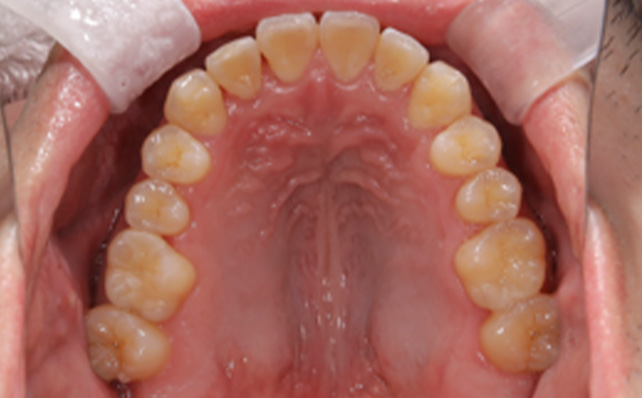

治療後